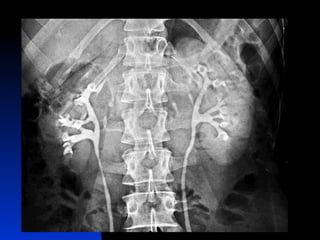

SISTEMA RENAL :     2 Rins    2 Ureteres   1 Bexiga urinária    1 Uretra